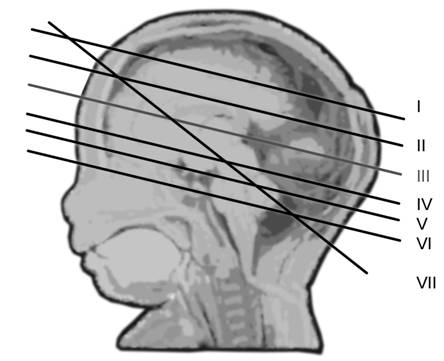

Fig. nr. 148 Planurile de sectiune transversala ecografica ale craniului fetal, demonstrate pe model anatomic (adaptat dupa Merz[8] )

Planul I - cel mai inalt plan axial. Cortexul cerebral hipoecogen localizat intre linia de mijloc si craniu.

Fig. nr. 149 Planul I de sectiune transversala.

Planul

II demonstreaza ventriculii laterali hipoecogeni si parte din plexurile

choroide ecogene.

Fig. nr. 150. Planul II de sectiune transversala a craniului fetal.

Planul III sau planul frontooccipital, pentru masurarea diametrelor biparietal si frontoocipital. Ecoul de mijloc frontoocipital este intrerupt in zona cavum septum pellucidi, anecogena, situata anterior de ventriculul III. Acesta este situat intre doi nuclei talamici hipoecogeni si apare ca o despicatura mica sau o linie.

Fig. nr. 151 Planul III de sectiune transversala a craniului fetal.

IV pune in evidenta ecoul liniei de mijloc, partial vizibil si mezencefalul

superior.

Fig. nr. 152. Planul IV de sectiune transversala

Planul V - trece prin partea bazala a mezencefalului si emisferele cerebrale. Pedunculii cerebrali formeaza aspectul de fluture, intre acestia apare fosa interpedunculara.

Fig. nr. 153. Planul V de sectiune transversala

Planul VI trece prin baza craniului si defineste fosele anterioara, mijlocie si posterioara. Osul sfenoidal hiperecogen apare la jonctiunea foselor anterioara cu posterioara. Portiunea joasa a cerebelului si puntea sunt vizibile.

Fig. nr. 154. Planul VI de sectiune frontala craniana.

Planul VII - plan oblic-transvers ce demonstreaza anterior cavum septum pellucidi si posterior cerebelul cu cisterna magna. In acest plan se poate evalua grosimea pliului nuchal intre 16 si 24 de saptamani (normal 5 mm) ce cuprinde tegument si tesut subcutanat, spre deosebire de translucenta normala din trim. I care este o acumulare de lichid.

Prin translarea sondei mai jos, se poate pune in evidenta foramen magnum.

Fig. nr. 155 Planul VII de sectiune craniana transversala.